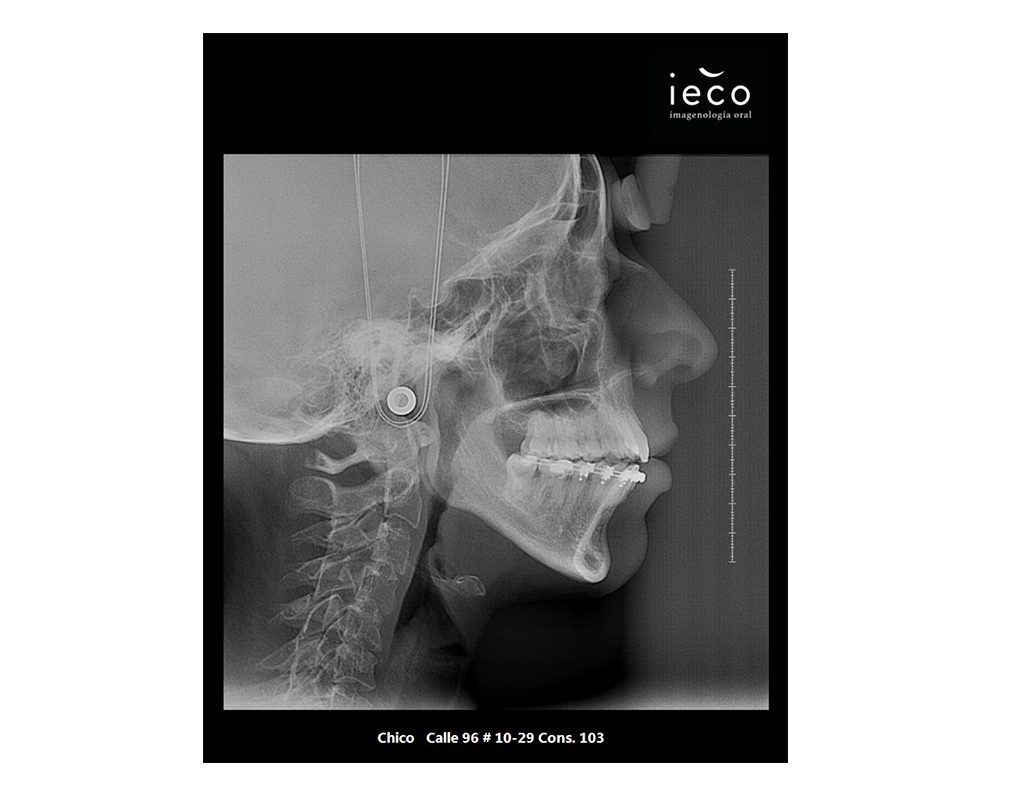

Radiografía cefálica/perfil

Es una imagen de la cabeza que muestra una vista lateral de los dientes y los maxilares, se utiliza para planificar tratamientos de ortodoncia y cirugía maxilofacial, al igual que el crecimiento facial.